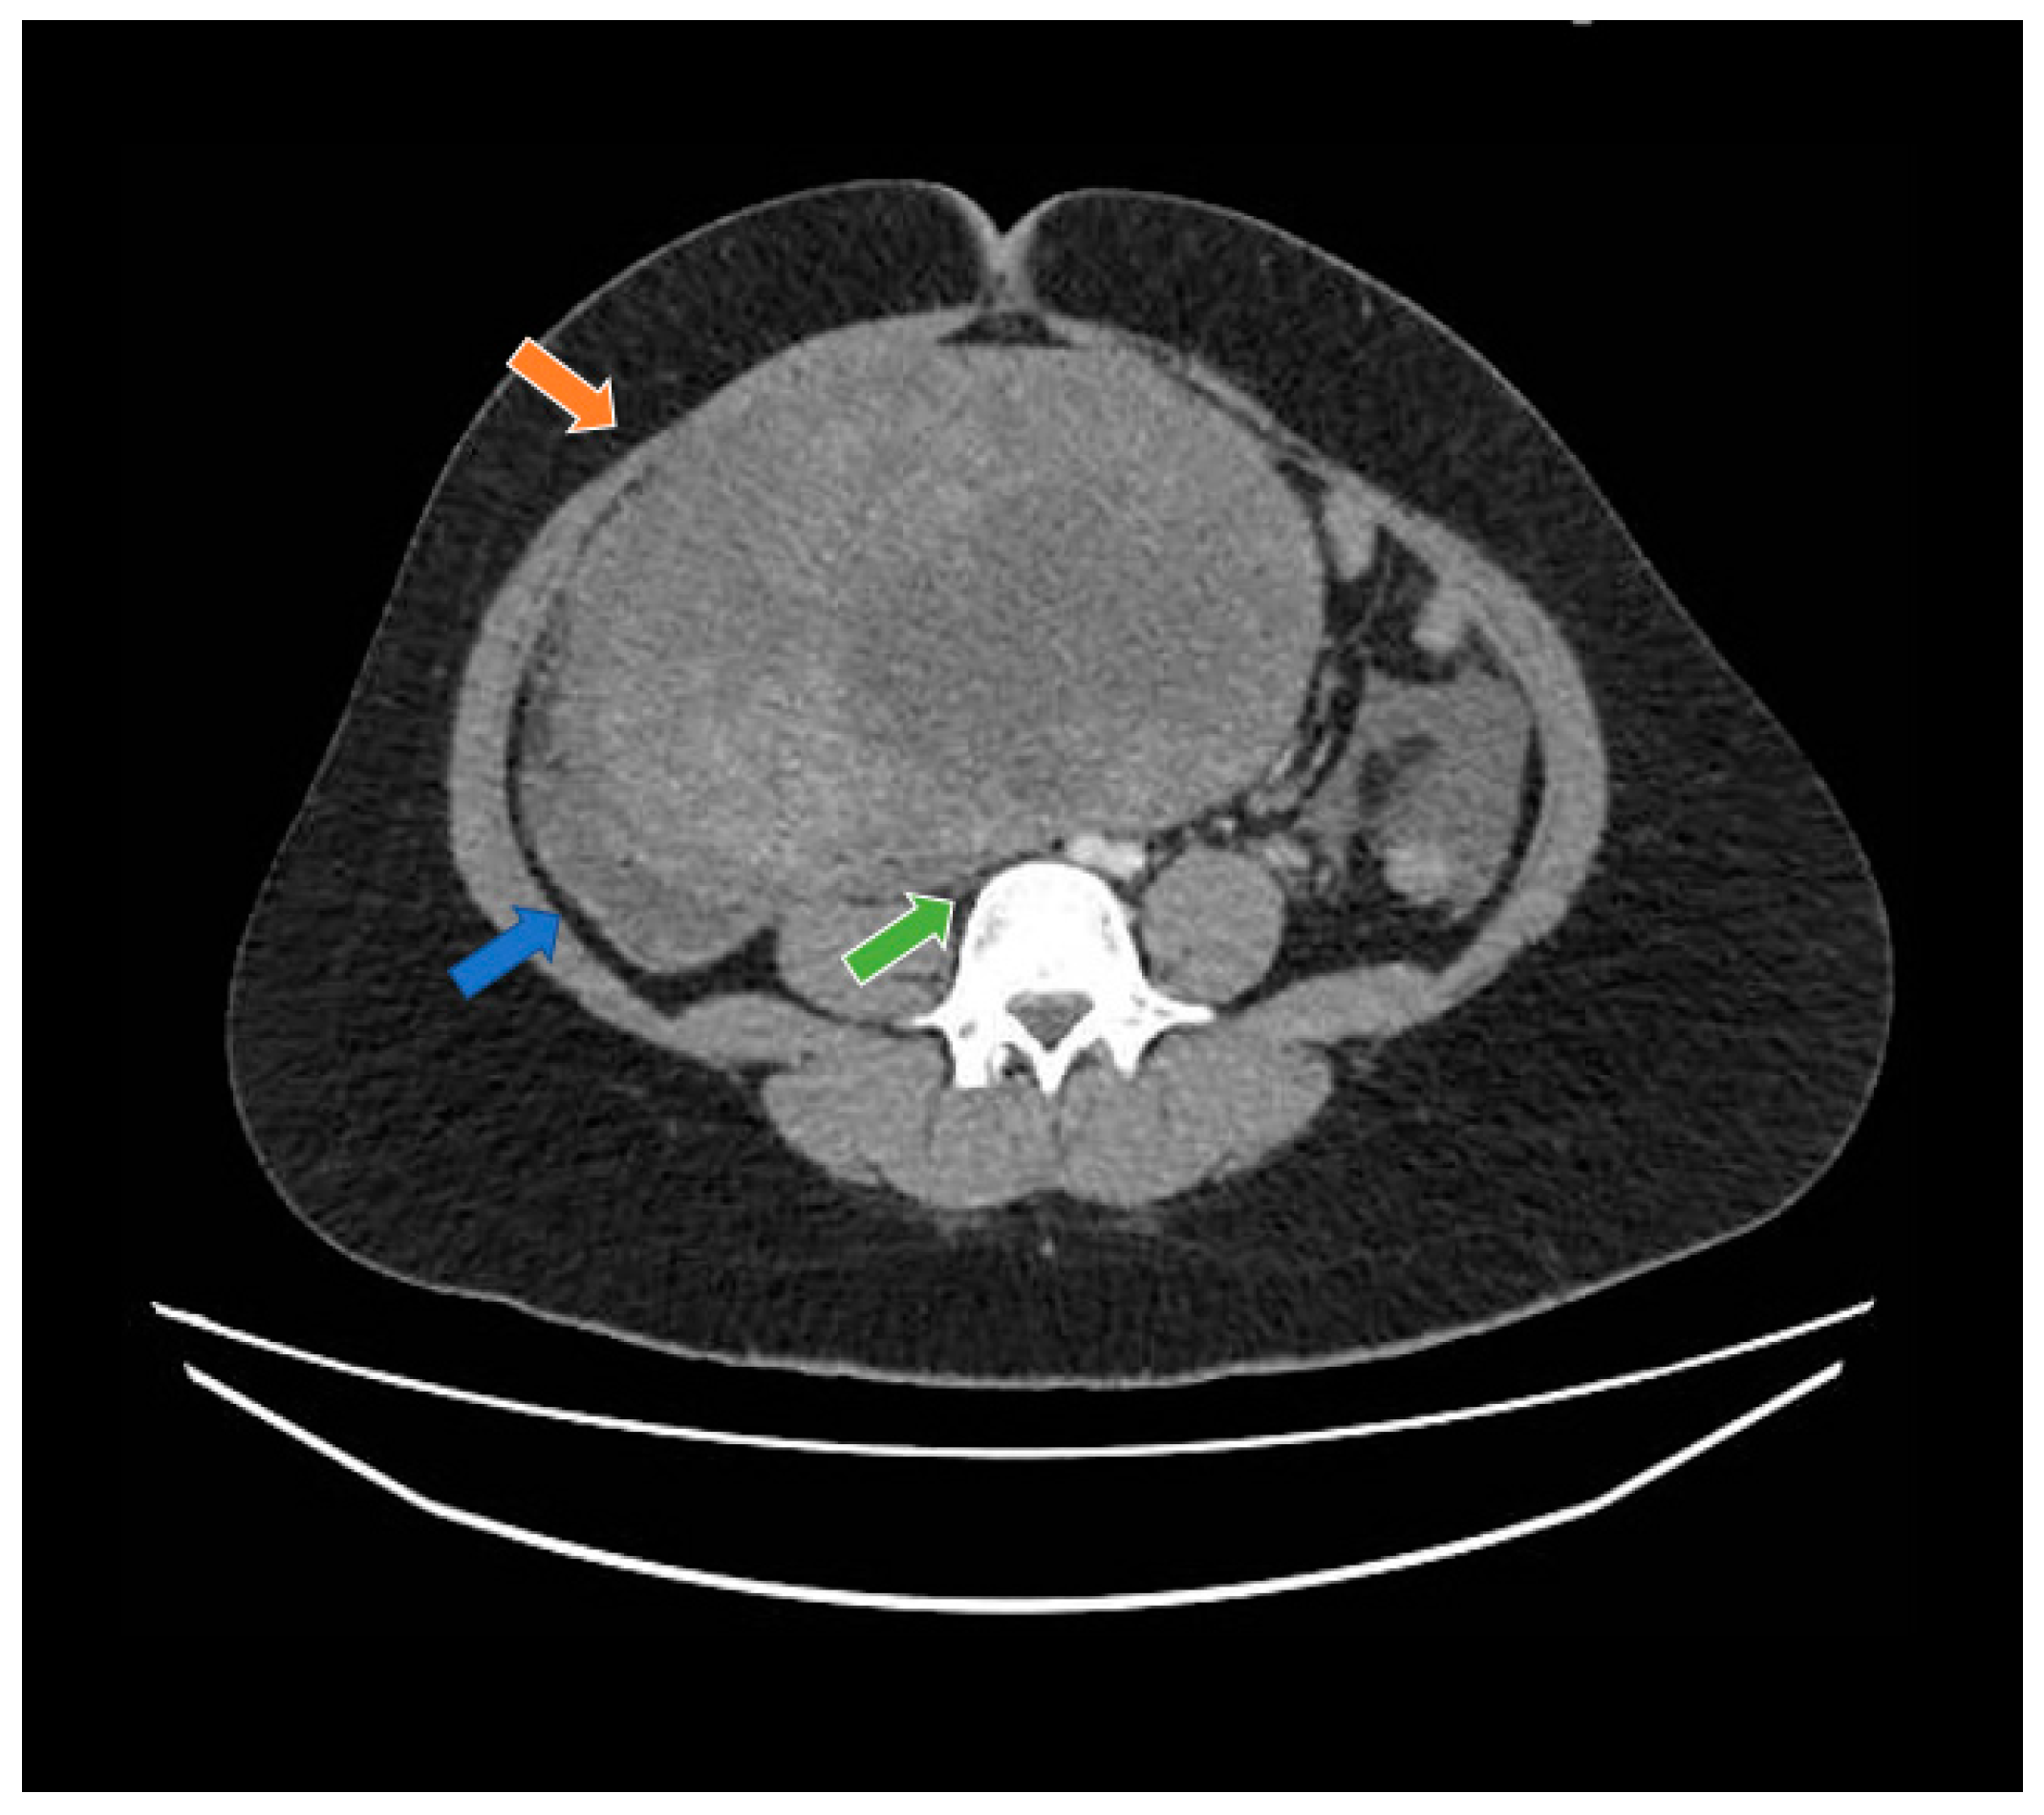

2. Case Report